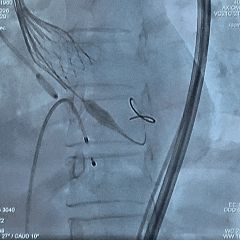

术中影像

双窦展开位根部造影

瓣叶狭窄明显,无明显反流

直头导丝顺利跨瓣

猪尾导管测量跨瓣压差约70mmHg

18mm球囊预扩,球囊上下滑动,无腰无漏,左冠显影,右冠无显影

输送系统顺利过弓

造影确认初始定位零位

瓣膜稳定展开

全展开位造影评估

瓣架呈直筒型,位置接近0位,少量反流

瓣膜缓慢脱钩,可见瓣膜实现自同轴,且无位移

脱钩后造影评估

瓣架形态佳位置可,冠脉显影,导丝压瓣可见反流

最终根部造影

撤出心室导丝后,反流明显减少